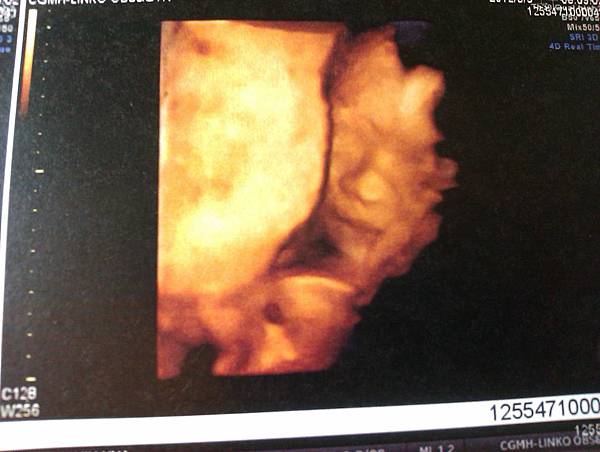

高層次超音波是在22週還是24週做的 (又忘了),因為是難得看得到小朋友的機會,行前十分期待。不過平常他很活潑的,今天卻睡得叫不醒,無緣親見他怎麼在肚子裏踢滾。

醫生量量小朋友身體各種長寬、心跳、臍帶血流,把十隻手指、腳趾一一數給我們看,沒有兔唇,然後問我們知不知道男女了?

答案揭曉,噹噹噹噹,是個小壯丁。臉長得有點像他爸爸啊。

小朋友的身長數據,比該有的週數平均值小了一週,同時胎盤上過早出現鈣化點,擔心是胎盤提前老化、營養輸送不夠。醫生建議抽血檢驗,先排除一些罕見因素的可能性,搭配觀察小朋友後續生長情況,再決定如何處置。